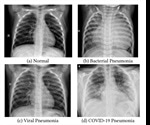

Transfer learning exploits chest-Xray to diagnose COVID-19 pneumonia